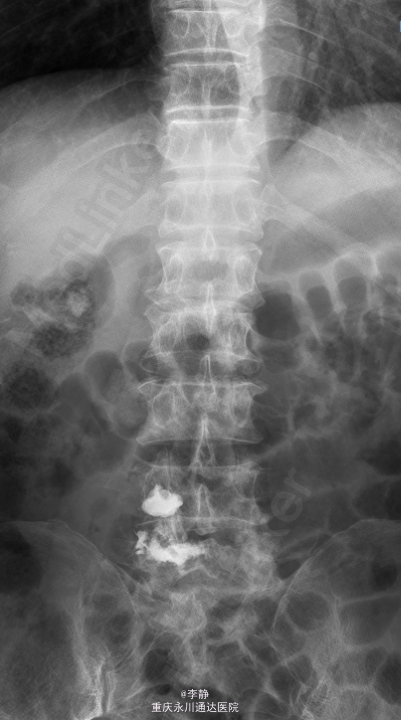

患者,男,63岁,因“腰痛、转侧不利3月”入院。 患者3月前无明显诱因下感腰背部疼痛,较剧,可忍,无外伤史,无双下肢麻木,无畏寒、发热,曾在当地医院就诊,查MRI提示腰椎多发椎体信号改变,考虑前列腺癌转移可能。

腰背部压痛,活动受限,直腿抬高试验阴性,双下肢肌力及肌张力无明显异常,双下肢末梢血运良好。MRI示腰椎多发椎体信号改变,考虑前列腺癌转移可能。

初步诊断:腰椎转移性肿瘤。局麻下行“L4.5椎体活检,椎体成形术”。局麻达成后常规经椎弓根进针,C臂机透视位置可,进针至L4椎体前下部,抓取少量组织送病理,提示“(腰椎)恶性肿瘤,转移癌首先考虑,待常规及免疫组化。”再进针至L5,透视正侧位位置满意,置入导管鞘,取球囊扩张器两侧透视下扩张至180psi,复位满意,取骨水泥C臂机透视下填充。